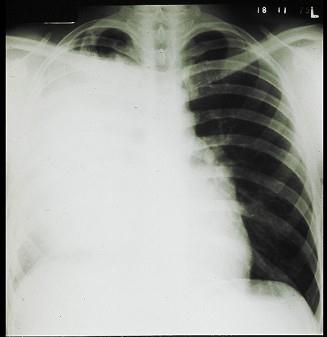

问题 男,62岁,刺激性咳嗽,痰血2个月,近两周来呼吸困难,半年前体检X线胸片未见明显异常。查体:气管右移,右胸廓下陷,叩实,可闻管状呼吸音,心界右移。X线胸片如图所示: 假设:纤维支气管镜活检找到肿瘤细胞,不可能是下列哪种细胞类型 ( )

选项 A、大细胞癌 B、乳头状瘤 C、小细胞癌 D、腺癌 E、鳞癌

答案 B